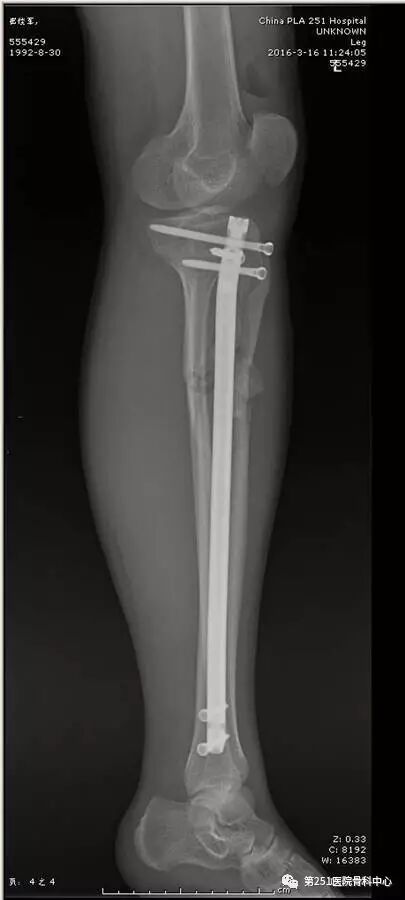

病例1:男性,40岁,车祸伤,胫腓骨多段骨折。

![]()